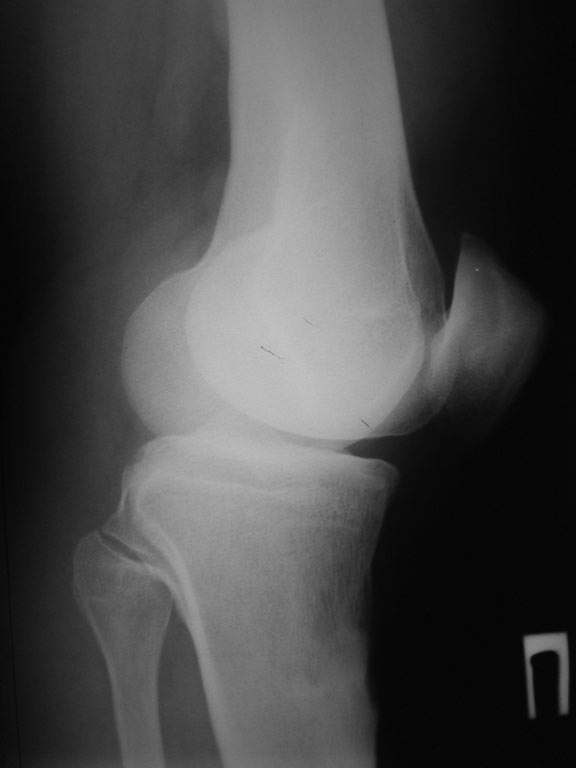

пациент наконец то объявился вновь и мы смогли выполнить новые снимки как лежа так и в нагрузке

Имя     : leja.jpg

Тип     : image/jpeg

Размер  : 17142 байтов

Описание: отсутствует

Url     : http://weborto.net:8080/pipermail/ortho/attachments/20080714/b21730ce/attachment-0003.jpg